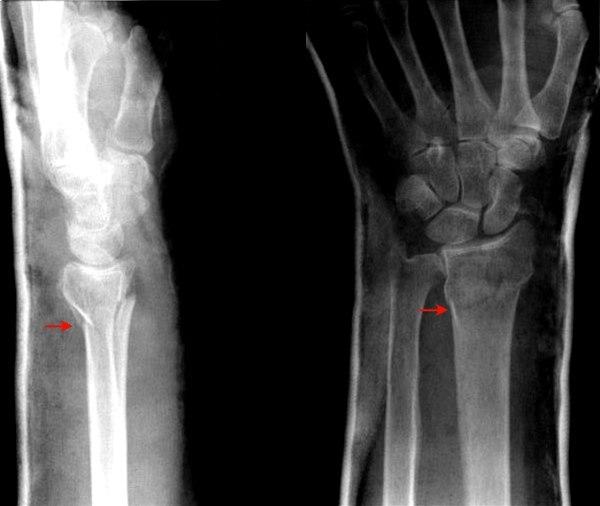

Beinbrudd

Det kreves en betydelig kraft for å brekke et bein, hvis da ikke beinet er svekket på forhånd av sykdom. Kraften kan være direkte, indirekte eller vridende. En direkte kraft, som et spark, vil brekke beinet på det stedet kraften treffer. Det vanligste beinbruddet er håndleddsbrudd etter fall. En indirekte kraft vil forårsake beinbrudd et stykke unna treffstedet. For eksempel vil et fall på en utstrakt hånd kunne føre til brudd på kragebeinet. En vridende kraft kan også brekke et bein, for eksempel hvis foten setter seg fast og den påfølgende vridningen fører til ankelbrudd.